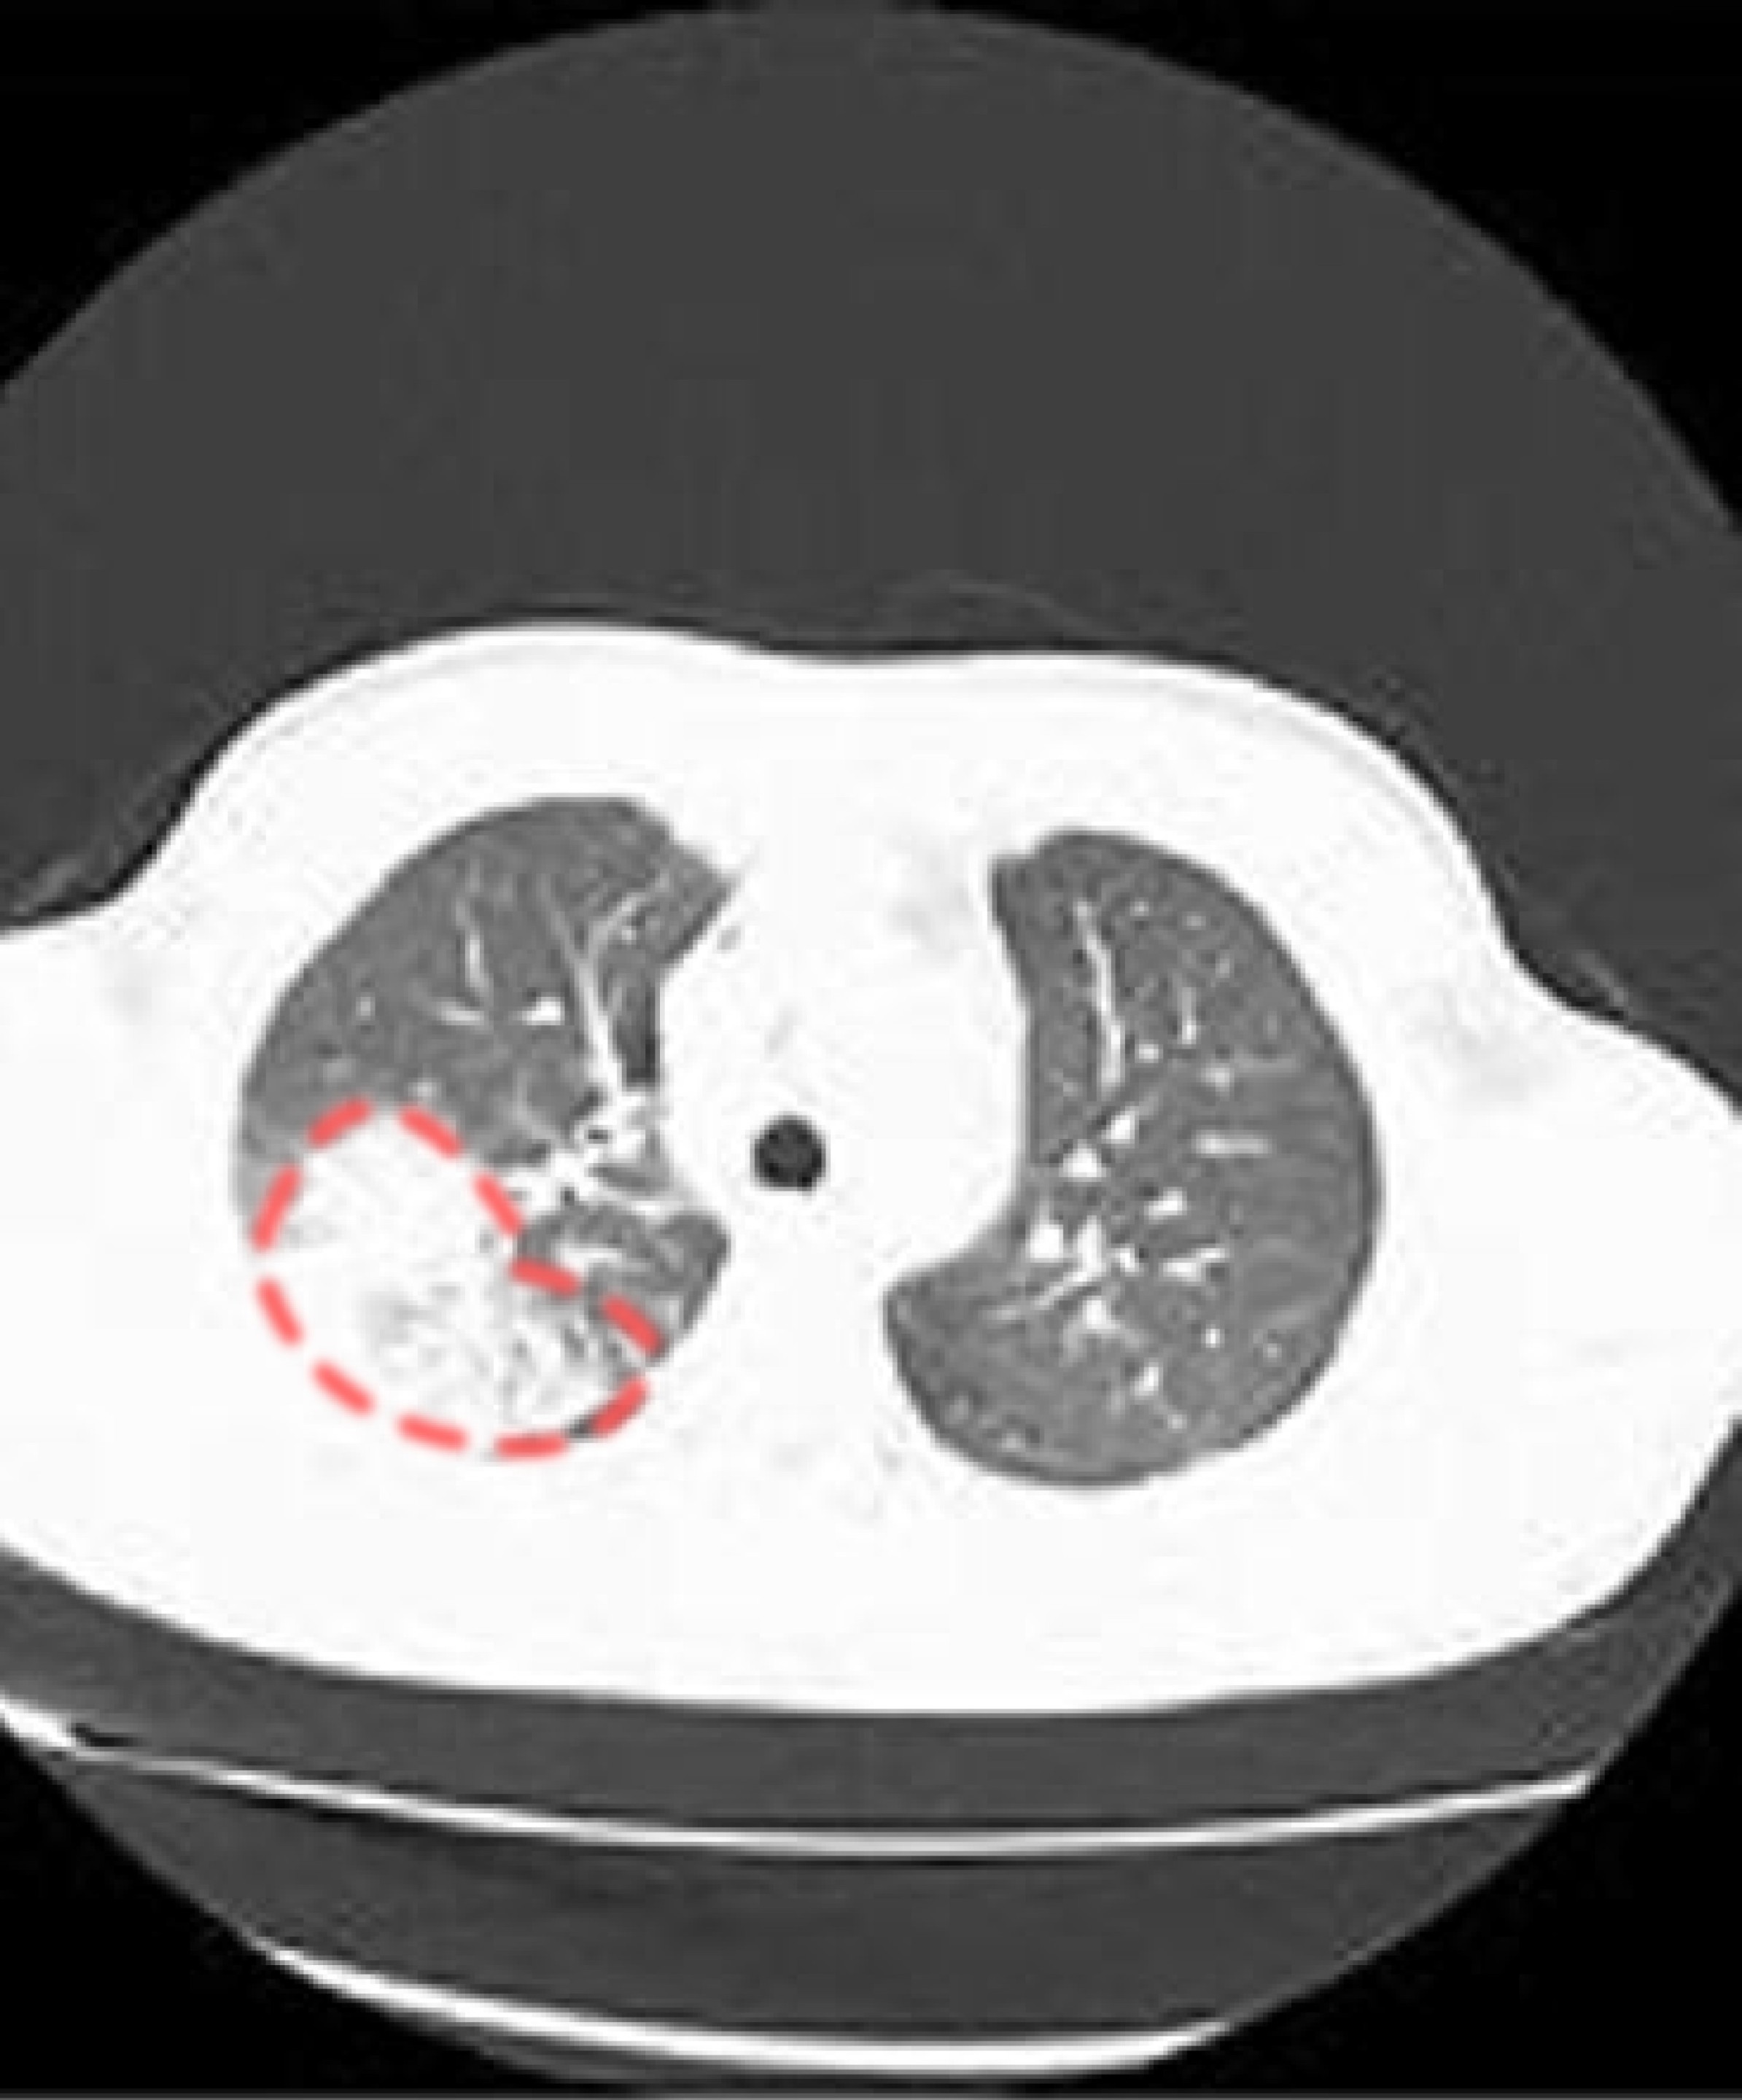

影像學檢查

| 胸部X光檢查 |

|

| 肺部電腦斷層掃描 (CT) |